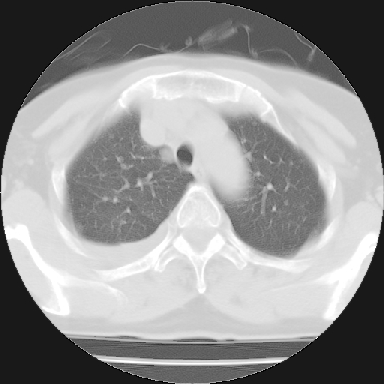

以下是引用苯小孩在2007-4-13 16:20:00的发言:[br]1、右下肺中央型肺癌并阻塞性肺不张、肺内转移、胸椎右侧附件亦有转移<横断层面第8层>.[br]2、右侧胸腔积液.

以下是引用swyyy2007在2007-4-13 15:31:00的发言:[br]右肺门下区肿块,右肺下叶支气管阻塞,右肺下叶不张,右侧大量胸腔积液,右肺中叶见结节状高密度影,边缘清,纵隔内见肿大淋巴结。首先考虑右下肺中心型肺癌伴右肺下叶不张、中叶、纵隔淋巴结转移。右侧胸腔积液。